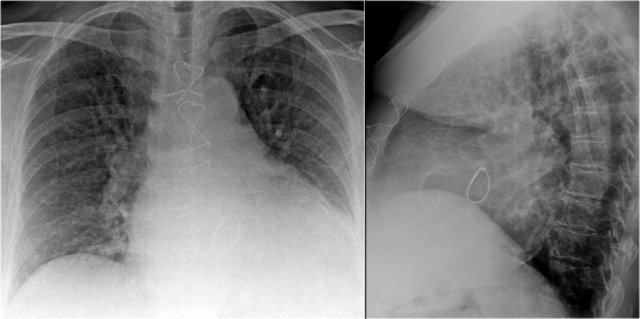

Case Example: Subtle Signs of Congestive Heart Failure

Begin by reviewing these current chest radiographs.

Based solely on these images, one might suspect congestive heart failure (CHF), though the findings are subtle.

Now review the previous study…

Scrolling between the current and prior films significantly increases diagnostic confidence in your diagnosis of congestive heart failure.

Key comparative findings include:

• Cardiac size: Slightly increased compared to the previous study; however, cardiomegaly was already present.

• Pulmonary vasculature: Mild vascular engorgement suggesting elevated pulmonary venous pressure.

• Interstitial markings: Subtle signs of interstitial edema .

• Pleural effusions: Bilateral small effusions, with subtle changes in the inferoposterior borders of the lower lobes, suggesting fluid accumulation.